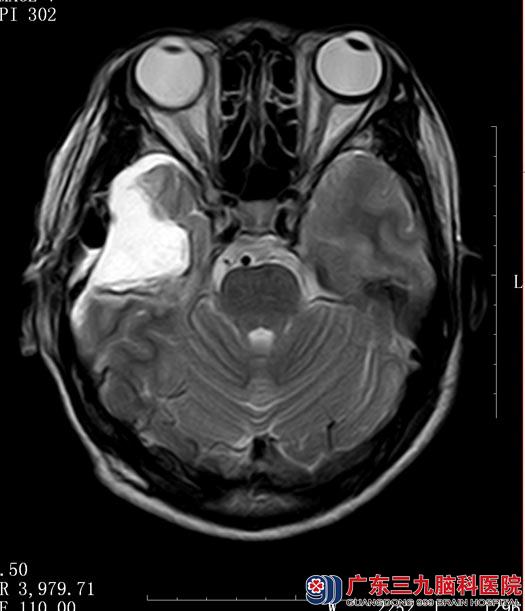

常规术前准备后, 5月11日,鲁明主任主刀在唤醒麻醉下行“右侧颞叶海绵状血管瘤切除+前颞叶切除术”。术中给予电生理监测,脑电图提示右侧颞叶皮质存在异常放电波;麻醉苏醒后,在患者语言及肢体配合下给予全切右侧颞叶海绵状血管瘤,沿右侧颞叶脑电图所示放电范围切除部分颞叶,再次监测皮层,未见异常放电。

术后陈女士未再出现肢体抽搐,四肢活动良好,术后病理结果示“海绵状血管瘤”。

▲手术后